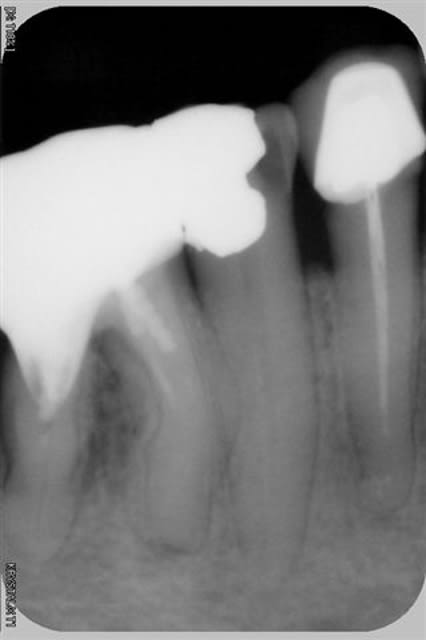

Est ce un fait exprès? Mais depuis mon retour, presque toute ma pratique tourne autour des reprises ENDO, et là, il faut que j'avoue toute l'admiration que j'ai pour les endodontistes exclusifs, c'est tout bonnement éreintant cette discipline, surtout lorsqu'on tombe sur des os!

Est-ce un fruit du hasard, mais les interventions que j'ai négociées représentent pratiquement tous les cas de figure qu'a traité Stéphane:

- fausse route bouchée au MTA

-instrument fracturé impossible à retirer, je suis passée à côté et je l'ai noyé dans la gutta chaude.

Et tout de même quelques racines domptées sans trop de difficultés!